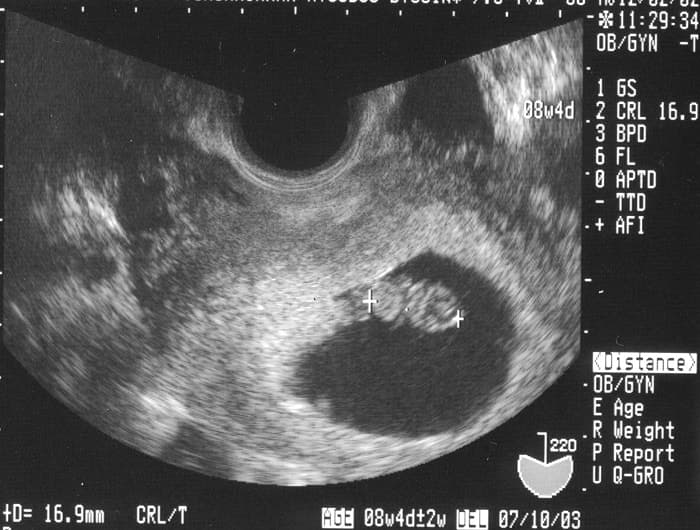

Siêu âm trong khám thai là một phương pháp khảo sát bằng hình ảnh học. Bác sĩ cho một phần của cơ thể tiếp xúc với sóng âm có tần số cao rồi theo dõi hình ảnh bên trong cơ thể.

Thời kỳ thai dưới 8 tuần tuổi (tức là 2 tháng thai kỳ đầu) cơ thể con đang dần hình thành và đồng bộ về các chức năng bộ phận, việc chiếu sóng điện từ có tần suất lớn ai dám chắc sẽ không gây cản trở quá trình hoàn thiện tự nhiên ở trẻ?